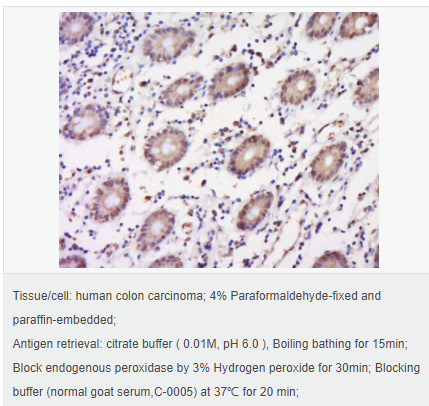

交叉反應(yīng):Human,Mouse,Rat(predicted:Pig,Cow,Rabbit,Sheep) 推薦應(yīng)用:WB,IHC-P,IHC-F,IF,Flow-Cyt,ELISA

| 產(chǎn)品應(yīng)用 | WB=1:500-2000 ELISA=1:5000-10000 IHC-P=1:100-500 IHC-F=1:100-500 Flow-Cyt=1μg/Test ICC=1:100 IF=1:100-500 (石蠟切片需做抗原修復(fù)) not yet tested in other applications. optimal dilutions/concentrations should be determined by the end user. |